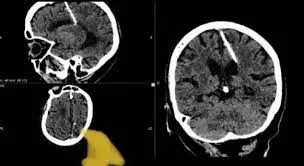

خبر اكتشاف إبرة في دماغ امرأة مسنة في الشرق الروسي، تُظهر حالة طبية غريبة أثارت الدهشة والتعجب. تفصيل هذا الحادث الطبي يعكس الجوانب المأساوية لتاريخ النزاع والحروب، خاصة خلال فترات الحروب العالمية.

التحليل الطبي لهذه الحالة أظهر أن الإبرة داخل الدماغ لا تشكل خطرًا كبيرًا على حياة المريضة. رغم أن هذه الإبرة لديها تأثير فتاك، فهي تعكس معاناة الأشخاص الذين عاشوا في ظروف قاسية خلال تلك الفترة الزمنية.